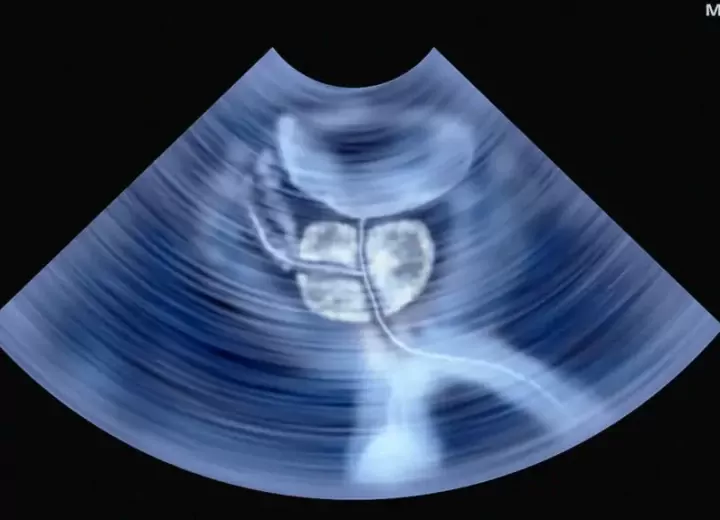

- трансректальная (взятие образца через прямую кишку под контролем УЗИ);

Трансректальная пункционная биопсия простаты является наименее болезненным и наиболее распространенным видом диагностики. УЗИ-аппарат помогает точно направить иглу для забора биоптата в подозрительные участки железы, не повреждая при этом окружающие здоровые ткани.

- Врач дезинфицирует зону ануса и вводит в прямую кишку тонкий УЗ-датчик с биопсийной насадкой.

- С помощью иглы медик выполняет проколы в подозрительных участках железы и делает забор фрагментов ткани.

За один сеанс биопсии простаты под контролем УЗИ берут пункцию из 10–12 участков железы. Исследование большого количества фрагментов позволяет снизить риск ложноотрицательного результата.